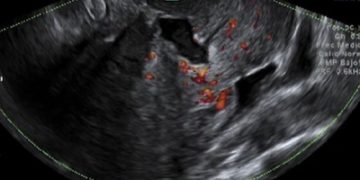

How To Do Giugno 2024: diagnosi e gestione delle anemie fetali

Cari soci, questo mese un nuovo video "How to do", dedicato alla diagnosi e alla gestione delle anemie fetali. Grazie a Tiziana Fanelli! Il video è accessibile ai soli soci...